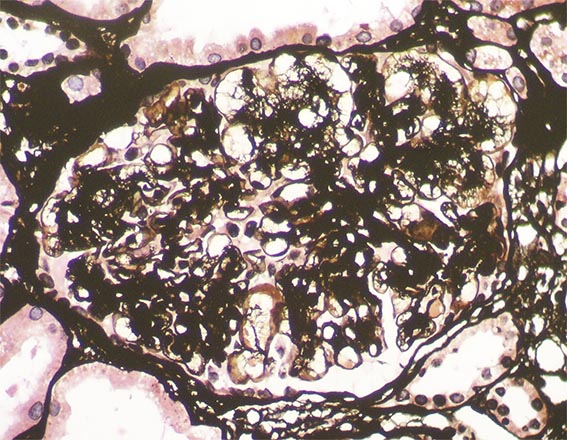

Figure 6. Methenamine-silver, X400.

Figure 7. Methenamine-silver, X400.